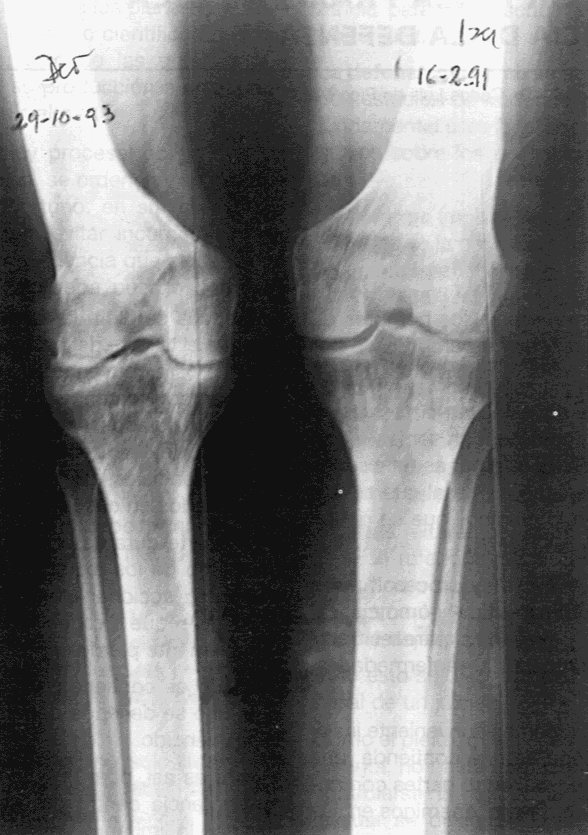

8 de diciembre de 1992 Rodilla izquierda en eje, mientras la rodilla derecha continúa valga

La osteotomía de la rodilla derecha, se realiza siguiendo las mismas indicaciones pre y postquirúrgicas a las que fue sometida la rodilla izquierda y se lleva a cabo dos años después el 29 de octubre de 1993.

Controles radiográficos demuestran consolidación en eje y dentro de los plazos establecidos para el tipo de osteotomía sin déficit de consolidación previstos por la patología renal.

Este es el punto saliente de nuestro trabajo, pues fue motivo de dudas prequirúrgícas al determinar la osteotomía previa al trasplante renal.

Por último, hoy á los 10 años de la primera osteotomía en su rodilla izquierda podemos observar radiográficamente que las dos osteotomías están consolidadas en eje e indoloras cumpliendo los movimientos comunes de la marcha sin claudicaciones.

Control realizado el 8 de julio del 2001 Osteotomías consolidadas y alineadas. Marcha normal